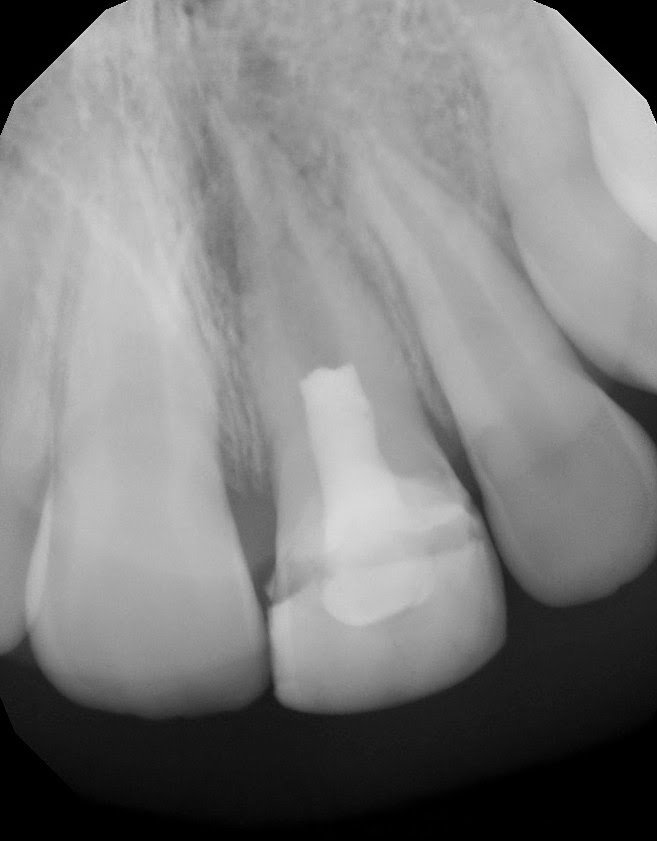

Following the treatment, a post operative flareup occurred – requiring antibiotics. I was concerned that this may be detrimental to the regenerative process. I am continually amazed at the healing capacity of the tooth. At 6 months, the tooth is aysmptomatic, fully function and canal is closing down. A dentin bridge is formed just below the MTA barrier. There is no additional plan for endodontic treatment on this tooth – unless eventually needed for restorative purposes.